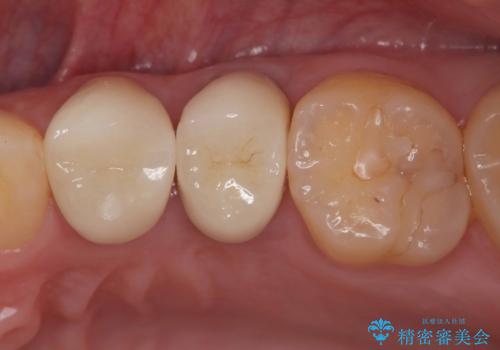

【セラミックインレー】被せ物が欠けた

- 奥歯の被せ物が欠けたを主訴に来院された患者様です。欠けてしまった被せ物を除去後セラミックインレーで治療を行いました。

欠けた範囲が大きく被せ物を外して後、セラミックインレーで治療を行いました。欠けたままの状態を放置しているとそこに食べ物が詰まり虫歯になってしまうので早めの治療が必要です。